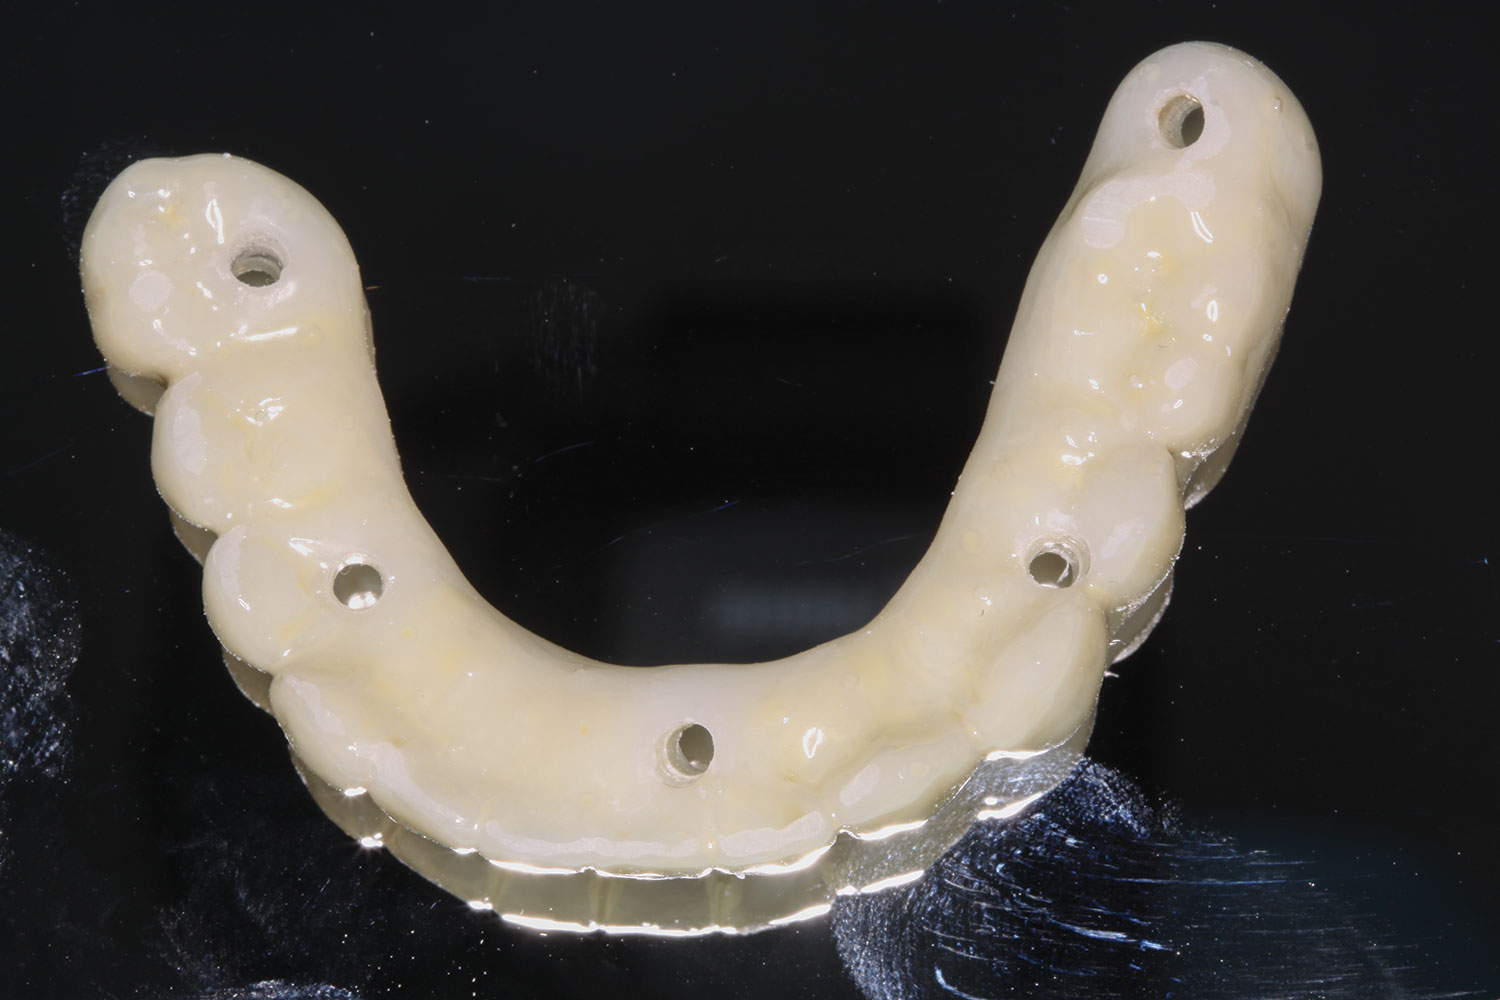

The implant company then returned an STL design file electronically via email. The office staff sent this file to the practice's 3D printer, and the appropriate color nanoceramic resin was used to print the prosthesis at 100 microns. Next, metal titanium (ti)-base cylinders, made specifically for the multi-unit abutments, were inserted into the prosthesis, which was then stained and glazed, and gingival color was applied to establish optimum esthetics (Figure 5).

Several hours later the dental team received the STL file, from which they would print the maxillary prosthesis on a 3D printer using appropriately colored nanoceramic resin. The prosthesis was stained and glazed, and metal cylinders were inserted into the undersurfaces

of the screw-access holes, each of which was specifically located to fit on the multi-unit abutments (Figure 16 and Figure 17).

Fig 5. Maxillary provisional prosthesis printed and ti-bases inserted.

Figure 5

Fig 16. Maxillary provisional prosthesis printed and ti-bases inserted.

Figure 16

Fig 17. Maxillary provisional prosthesis with screw-access holes in prosthetically correct locations.

Figure 17

Fig 31. Mandibular provisional prosthesis printed demonstrating screw-access holes in prosthetically correct positions.

Figure 31